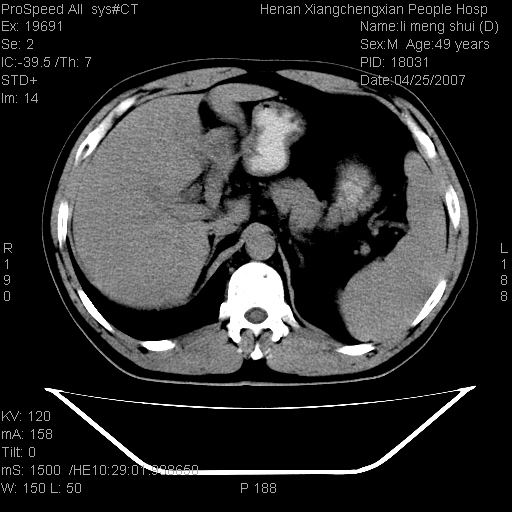

| 患者,男,49岁, 腹疼伴恶心\\呕吐20天,20天前无明显诱因出现右上腹部疼痛,钝疼,无放射,伴恶心\\呕吐,不伴发热.患者不愿增强. b超:肝脏右叶实性占位. ct:肝脏右叶可见一巨块状圆形低密度影,大小约93mm*84mm,其内可见点状高密度影,胆囊、胰腺、脾脏大小、形态及密度未见异常,腹膜后间隙未见肿大淋巴结影。 印象:肝脏右叶巨大肿块,性质待定,建议增强并穿刺活检进一步确诊。 ct平扫: ![]() ![]() ![]() ![]() ![]() ![]() ![]() ![]() ![]() ![]() ![]() ![]() ![]() ![]() ![]() ![]() ![]() 肝脏右叶肿块ct引导下穿刺活检术 患者于16时05分仰卧于ct检查台上,首先行肝脏ct扫描确定进针位置、深度、角度。在局麻下行ct引导下肝脏右叶肿块穿刺活检术。常规消毒、铺巾、局麻。在ct引导下使活检针经右侧腋中线、第9肋间隙垂直胸壁进针90mm,针头进入病变预定位置。在病变预定位置多点、多方向抽取小米样病变组织多块,涂片五张送病理检查。术后穿刺点局部无出血,未出现腹腔积液等并发症。术中及术后患者生命体征稳定,手术于17时10分成功完成。患者安返病房。 穿刺片 ![]() ![]() ![]() ![]() ![]() ![]() ![]() ![]() ![]() ![]() ![]() ![]() ![]() ![]() ![]() ![]() 病理结果肝细胞癌 ![]() 原贴地址:http://www.radinet.com.cn/forum_view.asp?forum_id=4&view_id=24130 ok |